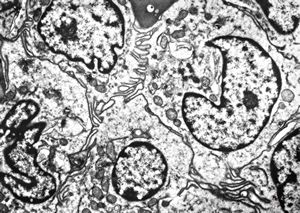

M,33y. | blood - hairy cell leukemia- ribosome-lamella complexin tricholeukocyte